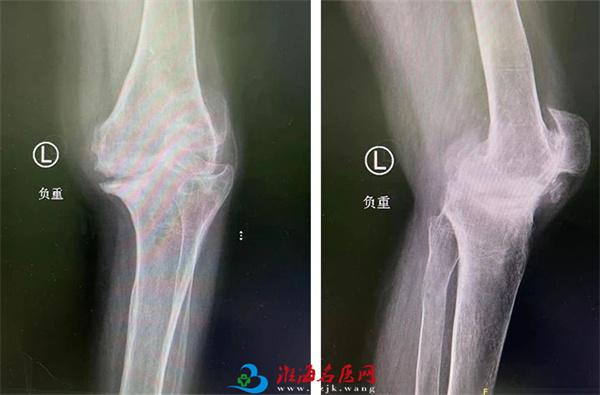

20年前,李大姐双膝关节出现疼痛症状,尤其是在劳累后这种疼痛感更重,当时在当地医院被诊为类风湿性关节炎,之后的时间里她一直以药物控制。但在10年前,李大姐双膝关节疼痛等症状明显加重,每天早晨还会有双膝僵硬的情况,尤其是左膝,在行走或其他活动时受限明显,严重影响日常生活。

术前

为求进一步治疗,李大姐在家人的陪伴下来到我院关节外科,经过相关系统检查后,确诊为类风湿性关节炎及双膝骨性关节病(KL分级 IV级)。